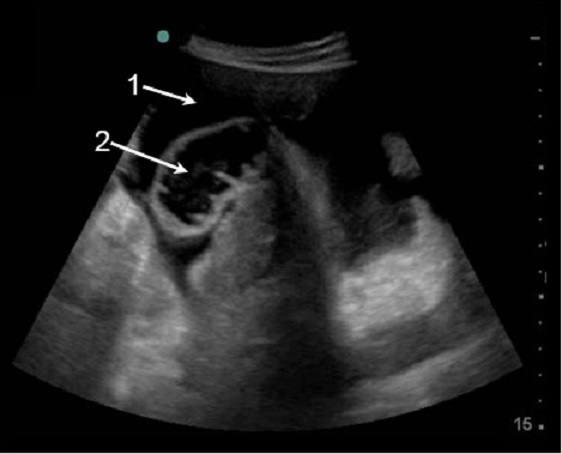

Gallbladder Ascites & Bowel Loops Image

Free Fluid

Bowel Loops